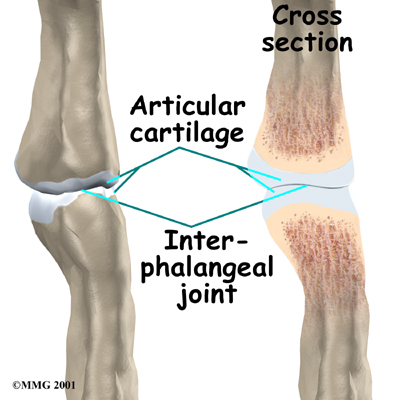

The finger and thumb joints are covered on the ends with . This white, shiny material has a rubbery consistency. The function of articular cartilage is to absorb shock and provide an extremely smooth surface to facilitate motion. There is articular cartilage essentially everywhere that two bony surfaces move against one another, or articulate.